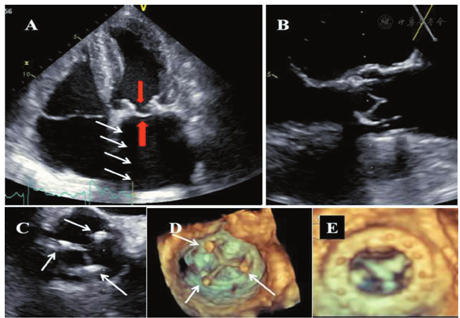

实时3D超声心动图,尤其是3D TOE检查对PHV的评价可提供比2D超声心电图更多的信息[22,23]。3D超声心动图面向瓣膜的外科切面对评价PHV功能非常有帮助,可识别反流束的存在、起源、方向及反流程度[11,24,25,26,27]。瓣周漏在3D超声上表现为缝合环外侧的回声失落,并可通过彩色多普勒进一步证实。3D超声可更好地显示PHV的结构如瓣叶、瓣环及其支撑结构。3D超声还用于评价血栓形成、血管翳及人工瓣膜开裂[28,29,30,31,32,33]。尤其当2D超声由于声影遮挡而造成图像质量差时,3D对于机械性二尖瓣及主动脉瓣的评价更具优势。2D超声不能显示的人工二尖瓣的心室面,通过3D超声可以显示[34]。

在经标准2D显像确定PHV最佳显示切面后,进行缩小扇角、3D放大和有或无彩色多普勒的全容积采集(心电图门控的单个心动周期或多个心动周期)。3D数据采集完成后,对图像任意切割以最优化显示心脏结构。通常将从LA面显示的二尖瓣图像旋转,使主动脉瓣位于12点位置、左心耳位于9点位置[11,26]。左、右冠状动脉窦之间的瓣叶联合处置于5点位置,而右冠窦与无冠窦之间的瓣叶联合处则置于8点位置。主动脉瓣瓣周漏常发生在右冠瓣与无冠瓣的交界区[35]。

应评价二尖瓣PHV的所有组成部分(缝合环、瓣叶、阀体、周围组织)。TTE是一线影像学检查,而当怀疑或确认存在瓣膜功能异常时则推荐TOE检查[15,21,27,29,137]。如有必要,可辅以荧光透视成像,心脏CT或CMR检查[40,43,65]。TTE检查需从胸骨旁长轴、短轴切面和多角度的所有心尖切面以及离轴切面上扫描整个缝合环、二尖瓣瓣下装置和瓣叶/阀体的运动情况。生物瓣膜的支架在心尖四腔心切面上显示最佳。彩色多普勒显像用于显示正常前向血流、预期的冲刷性血流和病理性反流。声影遮蔽效应可能导致不能良好显示二尖瓣PHV(尤其是机械性瓣膜)的LA侧(图5A,图5B)[88,89]。调整超声束与阀体开放的方向相平行则可改善瓣膜的显示质量。由于肋下切面遮挡效应最小,有助于显示人工瓣瓣周血流。TOE在检出和确定人工瓣MR的位置和机制方面常常优于TTE[149,150,151]。TOE显示LA和二尖瓣反流束更佳,但声影遮蔽效应限制了其对LV的显示(图5C,图5D)。在食管下段四腔心切面,通过旋转探头至二腔心和三腔心切面同时配合前屈、后屈时,反流束显示最佳。如在扇面中央进行适当调整,横向的经胃底短轴切面有助于显示瓣膜/缝合环的整个周长。TTE/TOE的长轴切面用于测量LVOT(见上文),而短轴切面则可确定任何瓣周漏的周向范围。3D超声心动图,尤其是与TOE相结合时,可理想地显示人工二尖瓣全貌、整个缝合环和瓣周反流的程度(图21)。

在彩色多普勒显像,瓣周漏具有典型的表现,即射流束沿人工瓣环外侧以偏心方向自LV进入LA。对于瓣周性MR的半定量评价,需要在缝合环水平的短轴切面上,仔细显示射流束颈部以精确测量其周向范围。反流的瓣周范围可表示为该周向范围占缝合环总周长的百分比(<10%为轻度;10%~29%为中度;≥30%为重度)[158]。人工瓣膜摇摆运动通常提示存在>40%的瓣环开裂,属于重度反流。